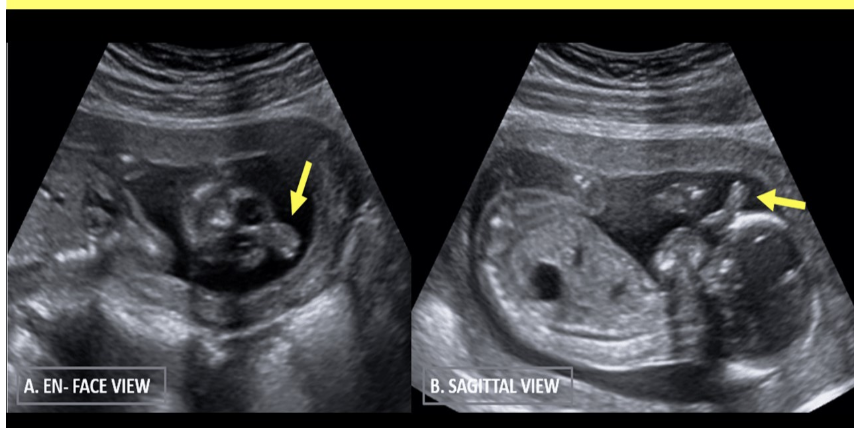

chorioangioma is supected. which image shows it

a) A

b) B

c) C

d) D